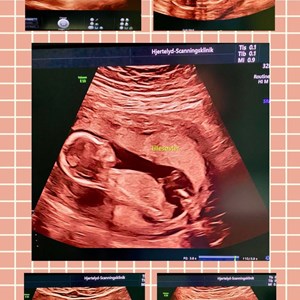

Hjertelyd - scanningsklinik for gravide

Tidlig scanning på foster uge 11+6 Når mor og far ser 1. gang hvor meget baby kan OG kan...